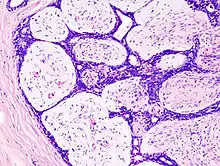

| Histopathologic image of breast fibroadenoma. Core needle biopsy. H&E stain. | |

Histopathologic image of breast fibroadenoma. Core needle biopsy. Hematoxylin & eosin stain.